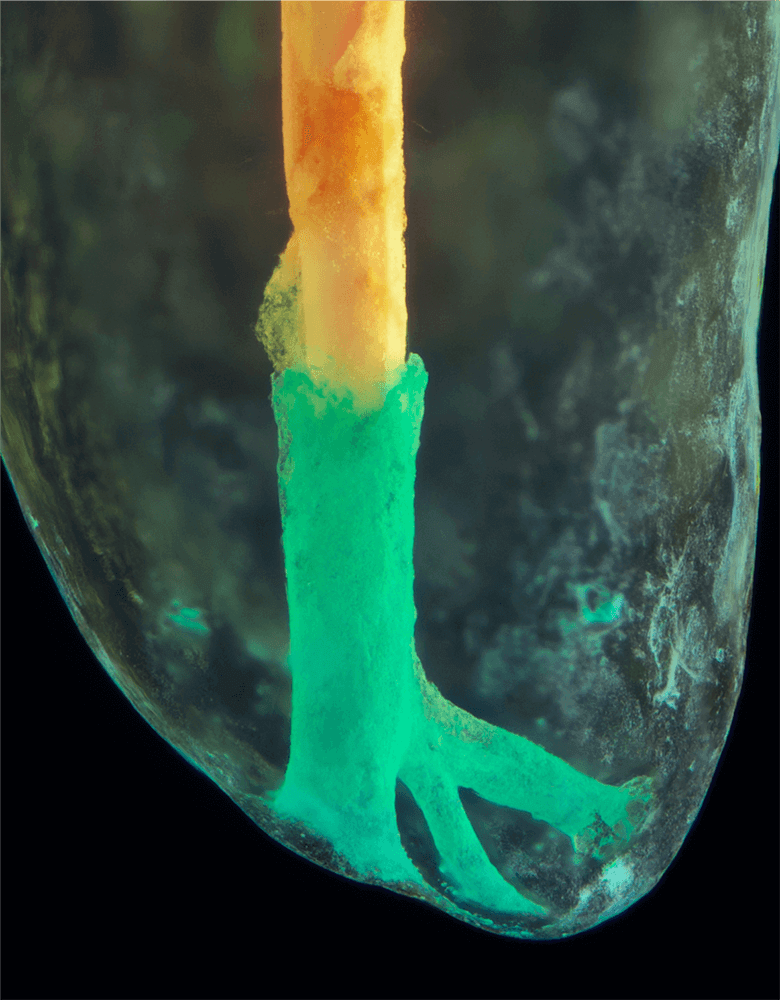

Das Verfahren, Zähne in durchsichtige Präparate zu überführen ist schon über 100 Jahre alt. Aber erst durch die Weiterentwicklung der alten Technik und die Kombination mit moderner Fotografie sowie der Entwicklung eines geeigneten Gefäßes zur Fotografie ist es meinem Vater Dr. Holm Reuver gelungen, einzigartige Bilder vom Inneren der Zähne aufzunehmen.

Die Bilder sind in verschiedenen Größen wählbar und auch als POPART-Variante erhältlich. Sie sind hervorragend geeignet für die Beratung von Patienten vor endodontischen Behandlungen, aber auch ein beliebter Eyecatcher im Wartezimmer. Außerdem haben die Bilder einen bedeutenden Stellenwert für die Erforschung der Pulpatopografie und für die Lehre im Bereich der Endodontie.

CLEARINGSERVICE bietet Ihnen die Möglichkeit, wurzelgefüllte Zähne mit der Technik des Transparentmachens untersuchen zu lassen. Das geht sehr einfach: Sie schicken uns den zu untersuchenden Zahn, dieser wird dann in ein transparentes Präparat überführt und mit hochwertiger Makrofotografie ausgewertet. Anschließend bekommen Sie die angefertigten Präparate zusammen mit der Fotodokumentation zugeschickt.